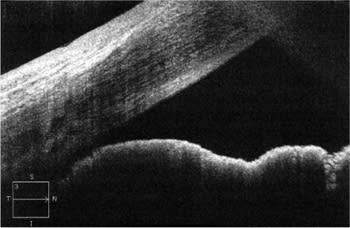

• Iris status: Using SD-OCT, we can examine the status of the iris and receive detailed answers to some very important questions: What is happening anatomically? Is the iris flat, convex or concave? Is the angle of incidence occludable or non-occludable (Figure 1)?

Figure 1. Large last roll of iris and occludable angle in plateau iris syndrome.